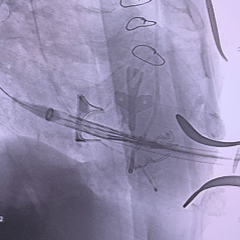

瓣膜重新释放至全展开位,可见位置合适,流出端可见形态压缩

超声评估瓣膜位置可,无瓣周漏

瓣膜稳定脱钩

28mm球囊后扩,瓣膜形态明显改善

最终评估可见瓣膜形态、位置均理想